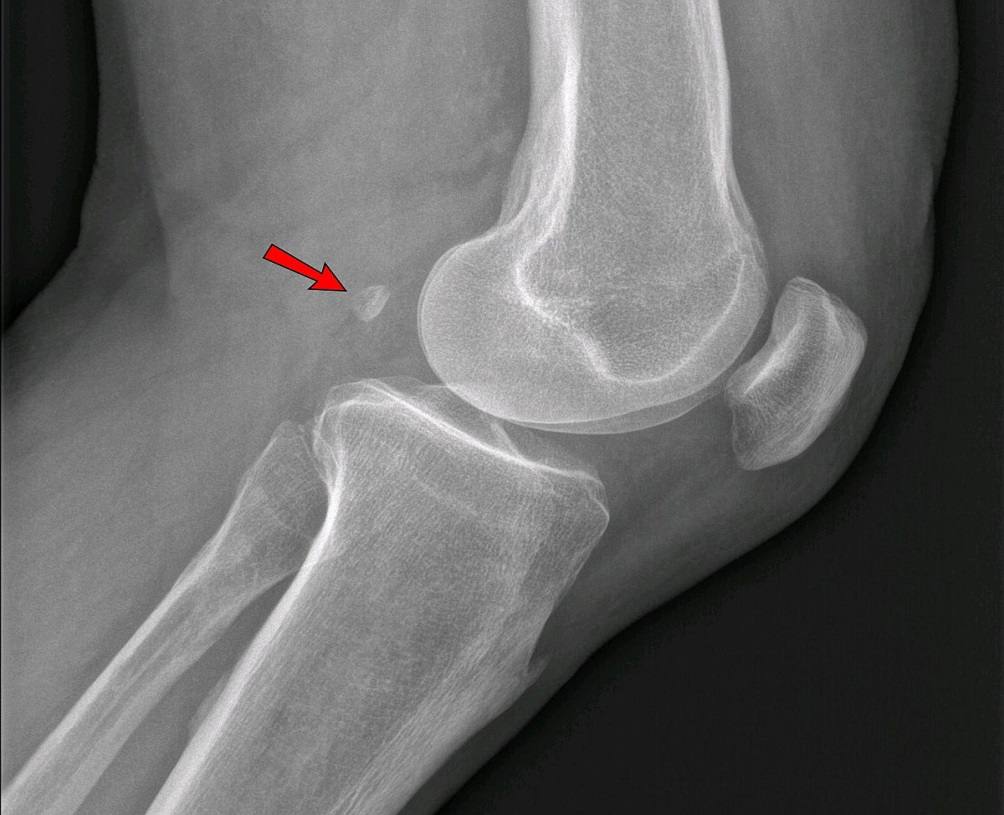

Фабелла коленного сустава, согласно анатомии, представляет собой сесамовидную кость, которая находится на внутренней стороне икроножной мышцы и крепится к заднему мыщелку бедра. Размер этой кости может варьироваться от 5 до 20 мм.

Для подтверждения диагноза и полной оценки состояния коленного сустава проводится тщательное физическое обследование пациента, рентгенография в боковой проекции, сонография и МРТ, чтобы исключить другие возможные патологии. Синдром фабеллы должен находиться под контролем ультразвукового исследования.